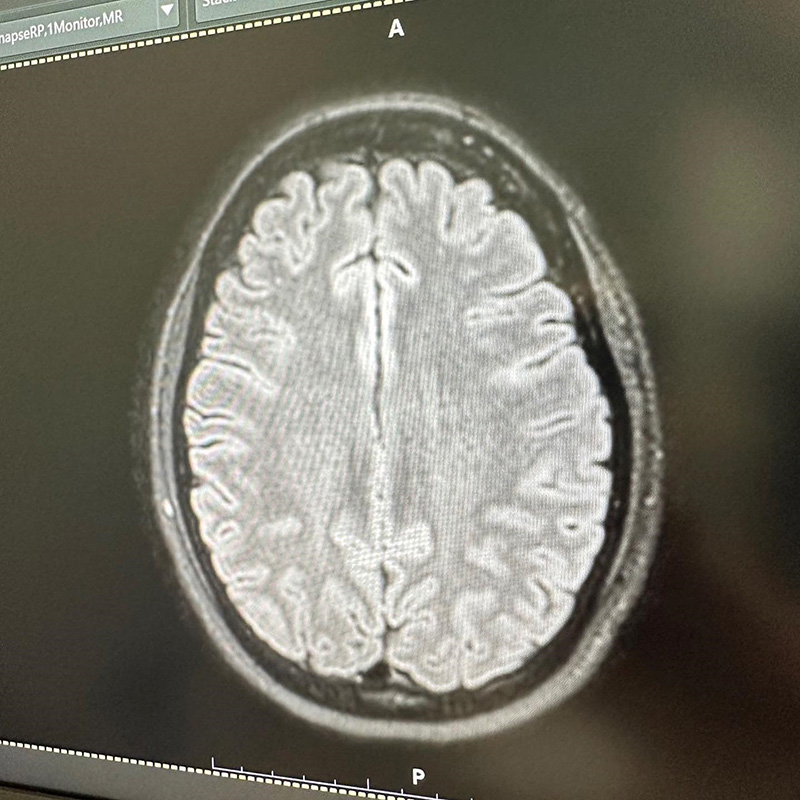

ตั๊ก บงกช เผยภาพ MRI สมอง ทำหลายคนเป็นห่วง เผยทำเพราะปวดหัวมาก นึกว่าเป็นเนื้องอก ก่อนพบเป็นไมเกรน ต้องฉีดยาอีก 3-6 เดือน

ทำเอาหลายคนเห็นแล้วอดเป็นห่วงไม่ได้ เมื่อล่าสุด (9 พฤศจิกายน 2566) ตั๊ก บงกช ได้เผยภาพ MRI สมอง ลงใน IG จนคนสงสัยว่าเกิดอะไรขึ้น ป่วยเป็นอะไรหรือเปล่า ซึ่งเจ้าตัวก็ได้บอกเล่าที่มาที่ไปของภาพนี้ว่า....

"MRI สมอง เพราะปวดหัวมาก สรุปเป็นไมเกรน นึกว่าเป็นเนื้องอก ลุ้นแทบตาย โล่งอก คุณหมอให้ยาฉีดที่ขาแต่เป็นยาฉีดสำหรับไมเกรน ดีขึ้นเลย แต่ต้องฉีดต่อเนื่อง 3-6 เดือน ดีจังไม่ต้องทนปวดกินยาแล้ว"